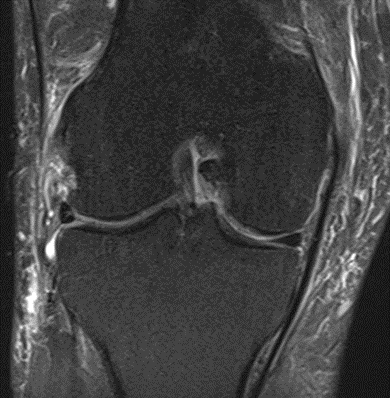

MRI scans illustrating the improvements regarding Group 2 are presented below, showing pre-treatment images with evident cartilage defects, pronounced bone marrow edema, and synovial inflammation, followed by post-treatment scans demonstrating improved joint structure, reduced edema, and decreased inflammation (Figures 12-29).

MRIs of Group 2

Figure 14: Male, 78 years, pre-intervention MRI.

Figure 15: Male of figure 14, two-month follow-up MRI: MSC plus ChondroFiller® liquid.